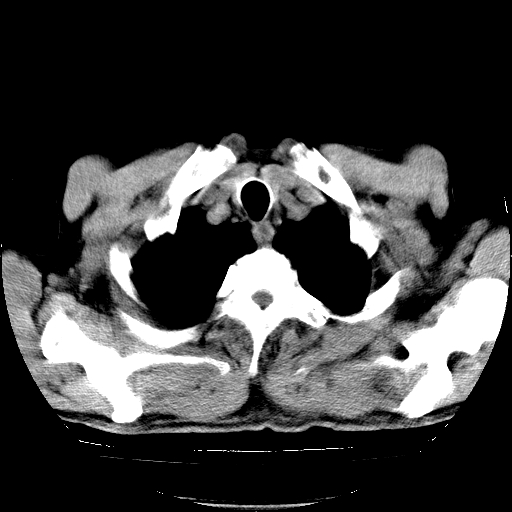

以下是引用hhcckk在2009-1-1 15:38:00的发言:[br]左下肺少许絮状模糊影--考虑感染[br]两肺散在小点状密度增高影--结合病史考虑矽肺?[br]气管壁钙化--可能由于老年退变性引起的